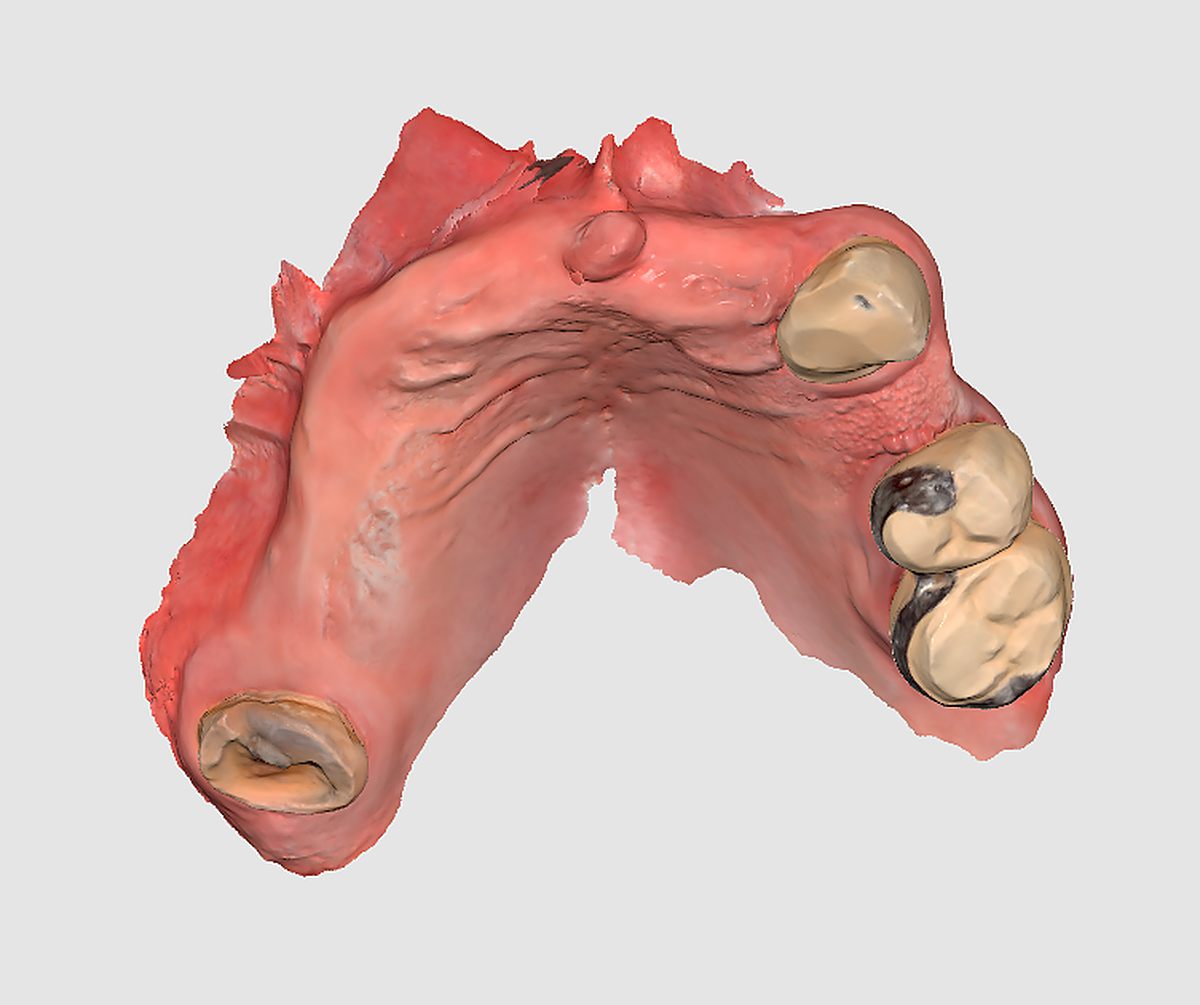

PASO 3. Elaboración de la férula o prótesis que servirá de guía para colocar los implantes.

El siguiente paso es elaborar una férula quirúrgica que hace las funciones de guía para colocar los implantes tal y como se ha planificado previamente. En el momento de la intervención, la prótesis se sitúa en la boca del paciente para atornillar con precisión milimétrica todos los implantes. “De esta forma nos aseguramos un menor riesgo para el paciente, un posoperatorio mejor y un menor tiempo de intervención para que se vaya a casa con unos dientes fijos en el momento”, asegura el doctor Alfonso Sanz Albornos.